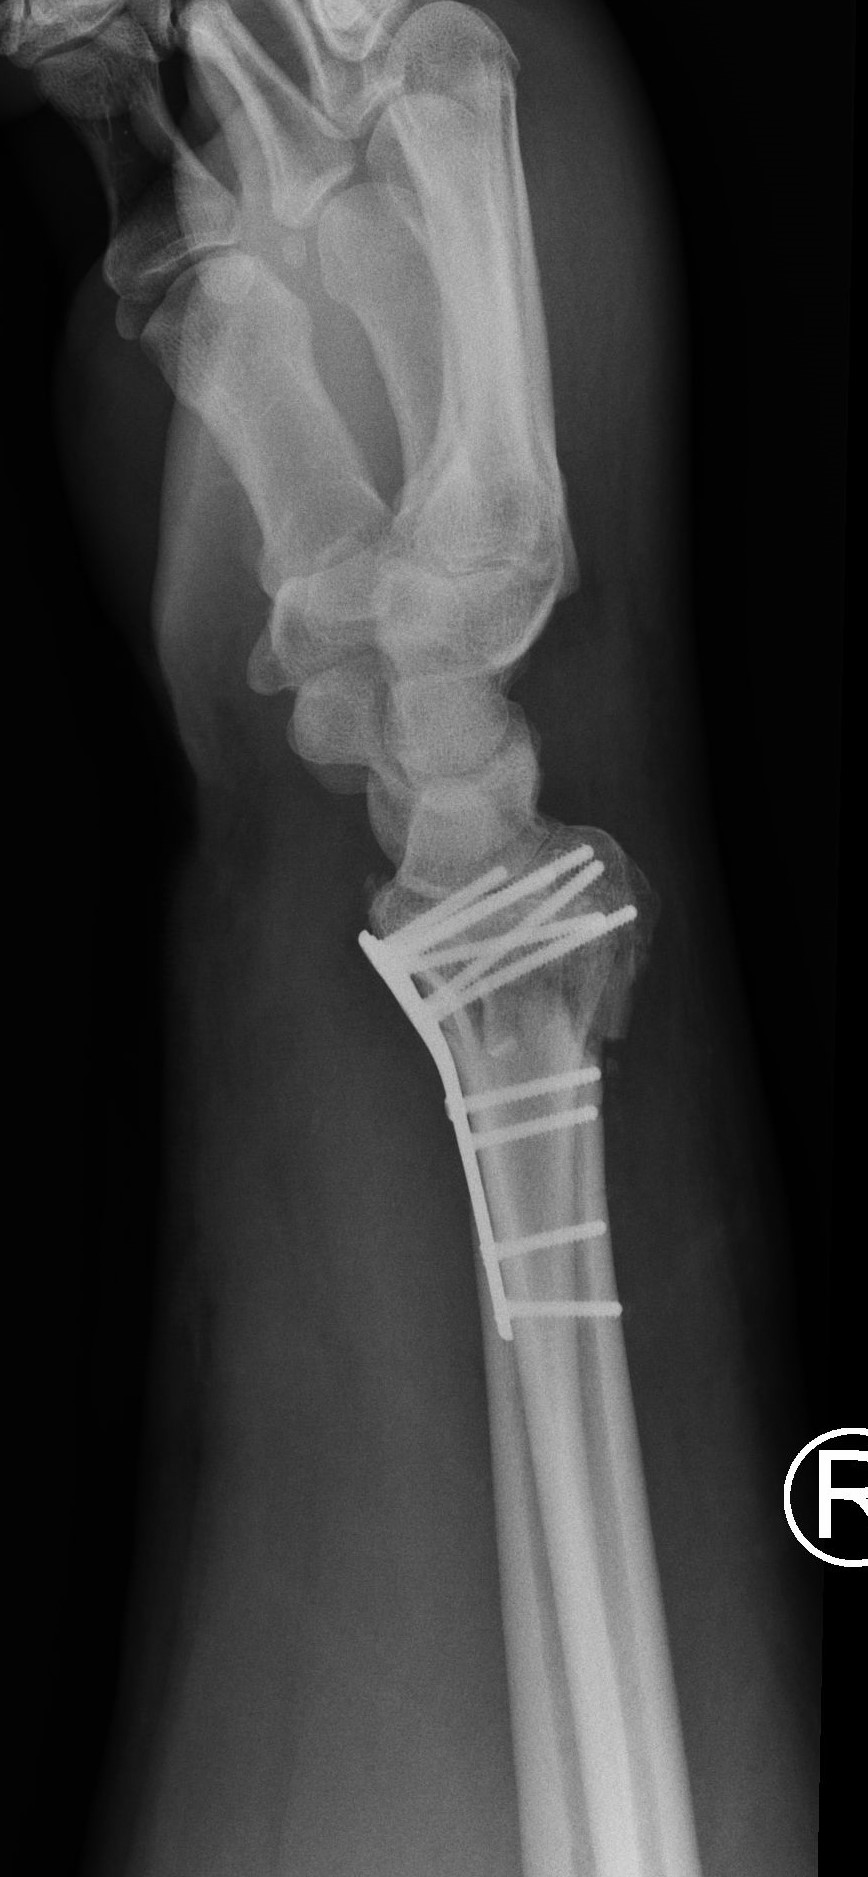

High-energy distal radius fractures are characterized by significant displacement of bone fragments, articular surface damage, and ligamentous injury. Tendon interposition between bone fragments occurs very rarely. In this report, we present a case of a complex distal radius fracture in which intraoperative findings revealed interposition of the flexor digitorum superficialis tendon of the index finger beneath one of the fracture fragments. The exceptional rarity of this situation prompted the authors to report this case.